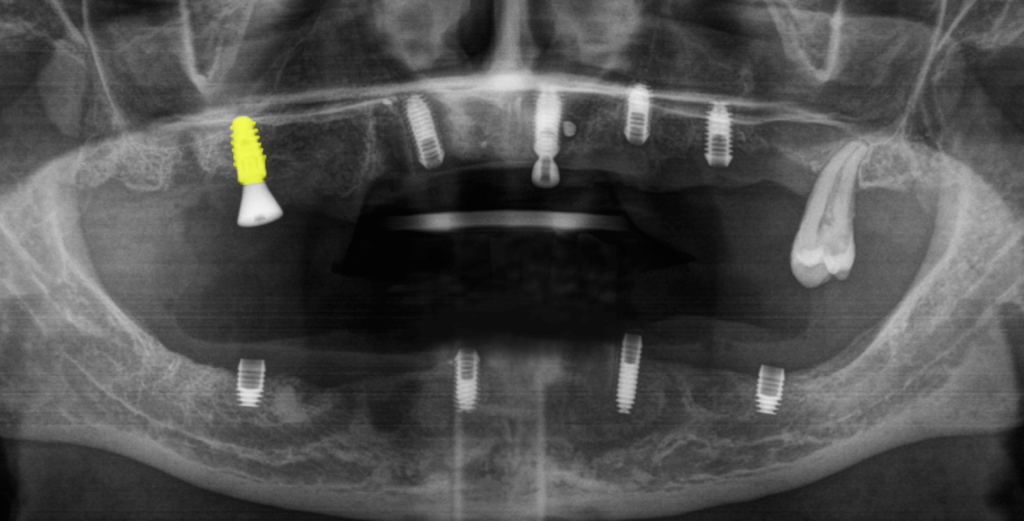

Согласно данным на снимке импланты были расположены не в одной плоскости (нарушена параллельность) и это могло вызвать сложность при протезировании цельнолитой конструкцией, однако при слаженной работе врача и зубного техника был шанс получить положительный результат.